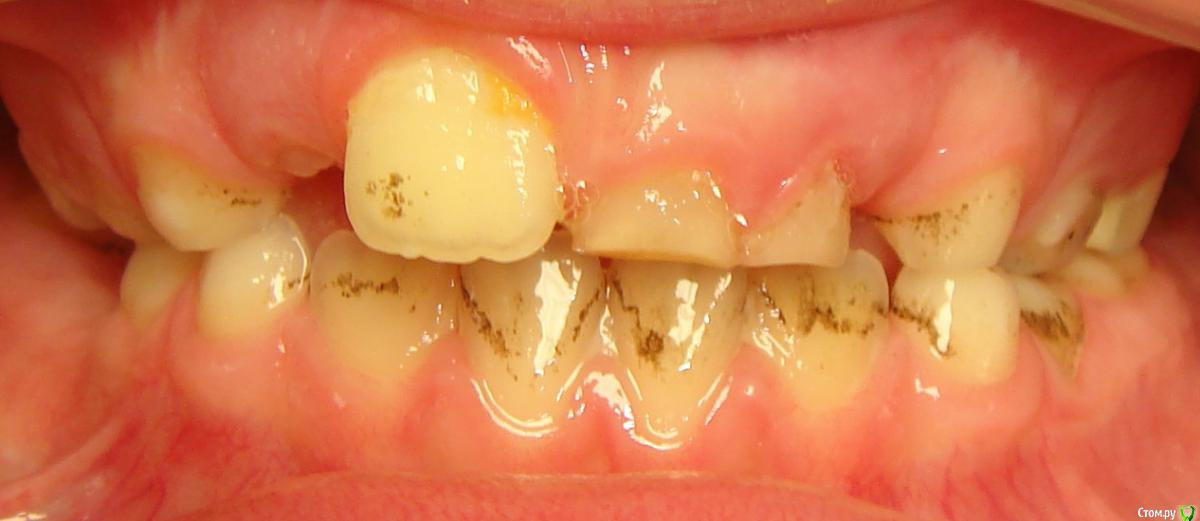

Opdihatop Опубликовано 9 января, 2017 Поделиться Опубликовано 9 января, 2017 Здравствуйте, коллеги! Хотел бы узнать ваше мнение по пациентке. Девочке 7 лет. План лечения в общем мне ясен и понятен. Меня интересует вопрос, когда лучше в данном случае убирать сверхкомплектный премоляр в области 21 зуба, потому что он начал двигать ц.л. вправо. Заранее спасибо! Ссылка на комментарий

Давлетшин Опубликовано 12 января, 2017 Поделиться Опубликовано 12 января, 2017 (изменено) С позиции детского амбулаторного хирурга-стоматолога я не трогал бы до окончания формирования корней, а 61, 62 убрал бы. Просто не лез, и не лезу. Да возможно есть есть очень хорошие хирурги с седацией и т.п. пусть они (он, она) решает. Из личного опыта у ребенка сверхкомплектный мешал прорезыванию 21 в семь лет, я все обьяснил сказал:" давайте ждать". Родители понимающе сказали:" давайте", и пошли снова к ортодонту, та в свою очередь отправила к своему "крутому" хирургу. Соответственно сверхкомплектный был удален (сверхкомлектный не прорезался) а у 21 сформирована была только коронка. Через три года, в 10 лет пришли снова, и у меня спрашивают:" где зуб"? Я направил на R-грамму, где увидел что коронка 21 "плавает" в очаге разряжения костной ткани размером 1.5*1.5 см. слизистая была в норме. Об"яснил, рассказал, показал риски для 11 и 22 зуба. и не сформированный 21 был удален. Причем после разреза слизистой и надкостницы с небной стороны сам выпал из полости "кисты". Не знаю где были ошибки. может мне надо было проявить эмоции и внушить что не надо удалять. Не знаю каков был ход операции, задели не задели ростковую зону 21 зуба, нарушили что нибудь не нарушили. Факт что ребенок остался без переднего зуба. Хорошо, мне хватило ума не лезть туда. Может ошибка родителей что не успокоились, и начали панику проявлять. Хирурга в той частной уже не было, наверно импланты крутит. Причем в разделе детская стоматология - есть мой фотоотчет по одонтоме. Т е если нет рисков повредить зачаток (зону роста корня)я лезу. Надо взвесить риски, сейчас что то делать, или же в 10-12 лет вытаскивать 21,22 зубы после формирования корней. Хорошо будет если срезы КТ добавите трансверсали. Даст Бог доучусь в орде на ортодонта, и начав работать ортодонтом думаю не изменю мнения при этом случае, зная работу детского хирурга. Снимков, КТ предоставить не могу потому, что шороха много было, оформления, переписывания карточки много было. Естественно когда я консультировал я все на словах говорил, через три года и не вспомнить. Ортодонт ни при чем, я типа не отправляла, они сами. Они кричали что именно ортодонт именно к определенному хирургу отправила, хирурга там уже давно и нет, и контора поменяла название. Кароч заведующая карточку под три замка в сейф свой убрала.Извините если много букв. Изменено 12 января, 2017 пользователем Давлетшин 1 Ссылка на комментарий

Yana guapa Опубликовано 13 января, 2017 Поделиться Опубликовано 13 января, 2017 убрать молочный ц. резец. подождать 6-8 месяцев хотя бы (лучше год) - все ростковые зоны уже значительно выше будут, хирург не задет уже.сделать КТ. и удалить сверхкомплектный. Дать возможность опуститься ц. резцу.сильно долго ждать (до полного формирования корней) не вижу смысла. Очень похожа ситуация была у моей девочки (такое же расположение). - очень долго не хотел ц. резец спускаться. Райц-терапия в помощь)) вышел)) Ссылка на комментарий

Yana guapa Опубликовано 19 января, 2017 Поделиться Опубликовано 19 января, 2017 Спасибо за снимки и рассказанный случай! конечно, и про такие истории надо знать! отправила к своему "крутому" хирургу. Соответственно сверхкомплектный был удален возможно он оказался не так крут! потому что многое действительно зависит от специалиста. Если элементарный зуб "самый крутой хирург в самой крутой клинике" удаляет ломая все стенки.... то что тут говорить про сверхкомплектный глубоко в кости, ростковые зоны и прочее... Поэтому все таки, я за удаление через 8 мес. у хорошего ответственного хирурга. Ссылка на комментарий